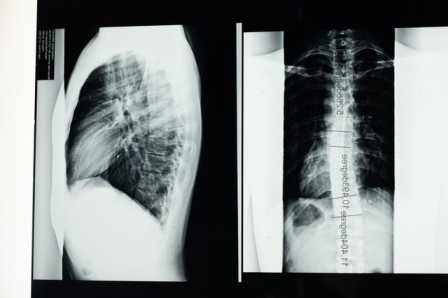

- इमेजिंग परीक्षण (एक्स-रे, सीटी स्कैन, एमआरआई स्कैन, पीईटी स्कैन, अल्ट्रासाउंड, एंजियोग्राफी): ये बृहदान्त्र की विस्तृत छवि प्राप्त करने के लिए किए जाते हैं।